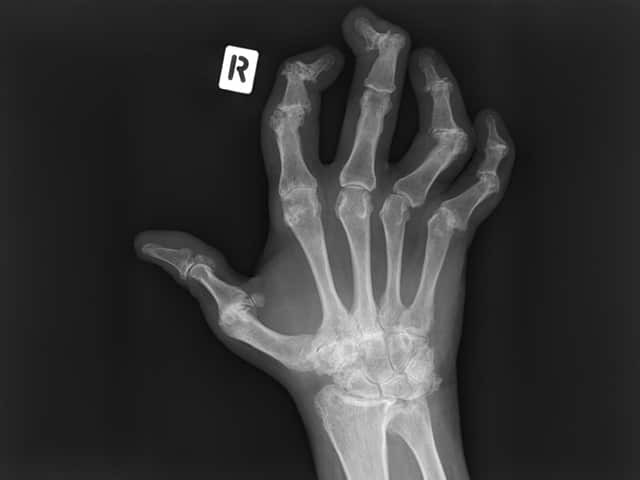

X-ray findings that are characteristic of psoriatic arthritis include:

Right hand